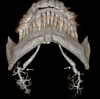

Methods: Patients with parotid or submandibular salivary symptoms were examined by 3D-CBCT sialography. They received an intraductal injection of 0.5 mL of water-soluble contrast medium maintained in the gland, followed by examination in a NewTom wide-field CBCT device. Images were processed with multiplanar and 3D reconstructions.

Results: A ductal exploration could be performed until the fourth divisions. The main lesions found were stones, stenosis, dilatations and "dead tree" appearance of the ductal system. No side effects of the catheterization or the iodine contrast were reported, nor tissue damages related to the contrast keeping technique.